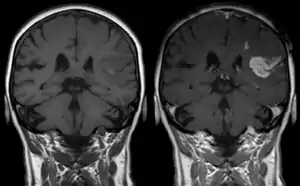

Effect of contrast agent on images: Defect of the blood–brain barrier after stroke shown in MRI. T1-weighted images, left image without, right image with contrast medium administration

Gadolinium(III) containing MRI contrast agents (often termed simply "gado" or "gad") are the most commonly used for enhancement of vessels in MR angiography or for brain tumor enhancement associated with the degradation of the blood–brain barrier. For large vessels such as the aorta and its branches, the gadolinium(III) dose can be as low as 0.1 mmol per kg body mass. Higher concentrations are often used for finer vasculature.[3] Gd(III) chelates do not pass the intact blood–brain barrier because they are hydrophilic. Thus, these are useful in enhancing lesions and tumors where blood-brain barrier is compromised and the Gd(III) leaks out. In the rest of the body, the Gd(III) initially remains in the circulation but then distributes into the interstitial space or is eliminated by the kidneys.